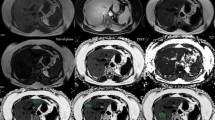

Post processing

The original MR images were processed using the Philips IPS workstation to generate pseudo-color maps. Two experienced radiologists (with 3 and 6 years in abdominal radiology) measured the FF values of left hepatic lobe, right hepatic lobe, whole liver, spleen, pancreatic head, pancreatic body, pancreatic tail, left and right kidney, L3 vertebra, psoas muscle at the level of L3 vertebra (hereinafter referred to as FFLL, FFRL, FFWL, FFSp, FFPH, FFPB, FFPT, FFLK, FFRK, FFL3, FFPM) and the fat areas(S values) of the abdominal cavity. Due to the large volume of the liver and spleen, the volumes region of interest (VOIs) were delineated. Other organs were small, and regions of interests (ROIs) were placed in the layer. S values included the total fat area of the abdomen at the level of the L3(S1), the internal abdominal fat area of organs (S2), and S3 referred to the ratio of S2 to S1 (Fig. 1).